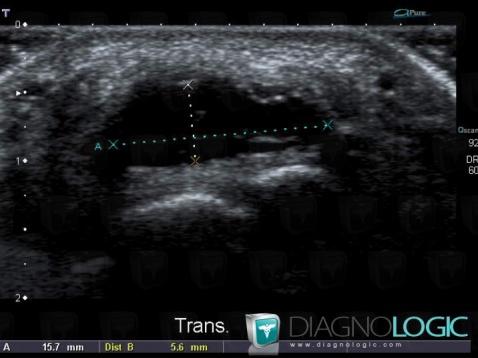

Synovial cyst, Other soft tissues/nerves - Hand, US

Here is the specific information in the key image above:

- Diagnosis Synovial cyst (link to Ganglion cyst), Location(s) Other soft tissues/nerves - Hand, with gamuts Cystic and cystic-like soft tissue mass